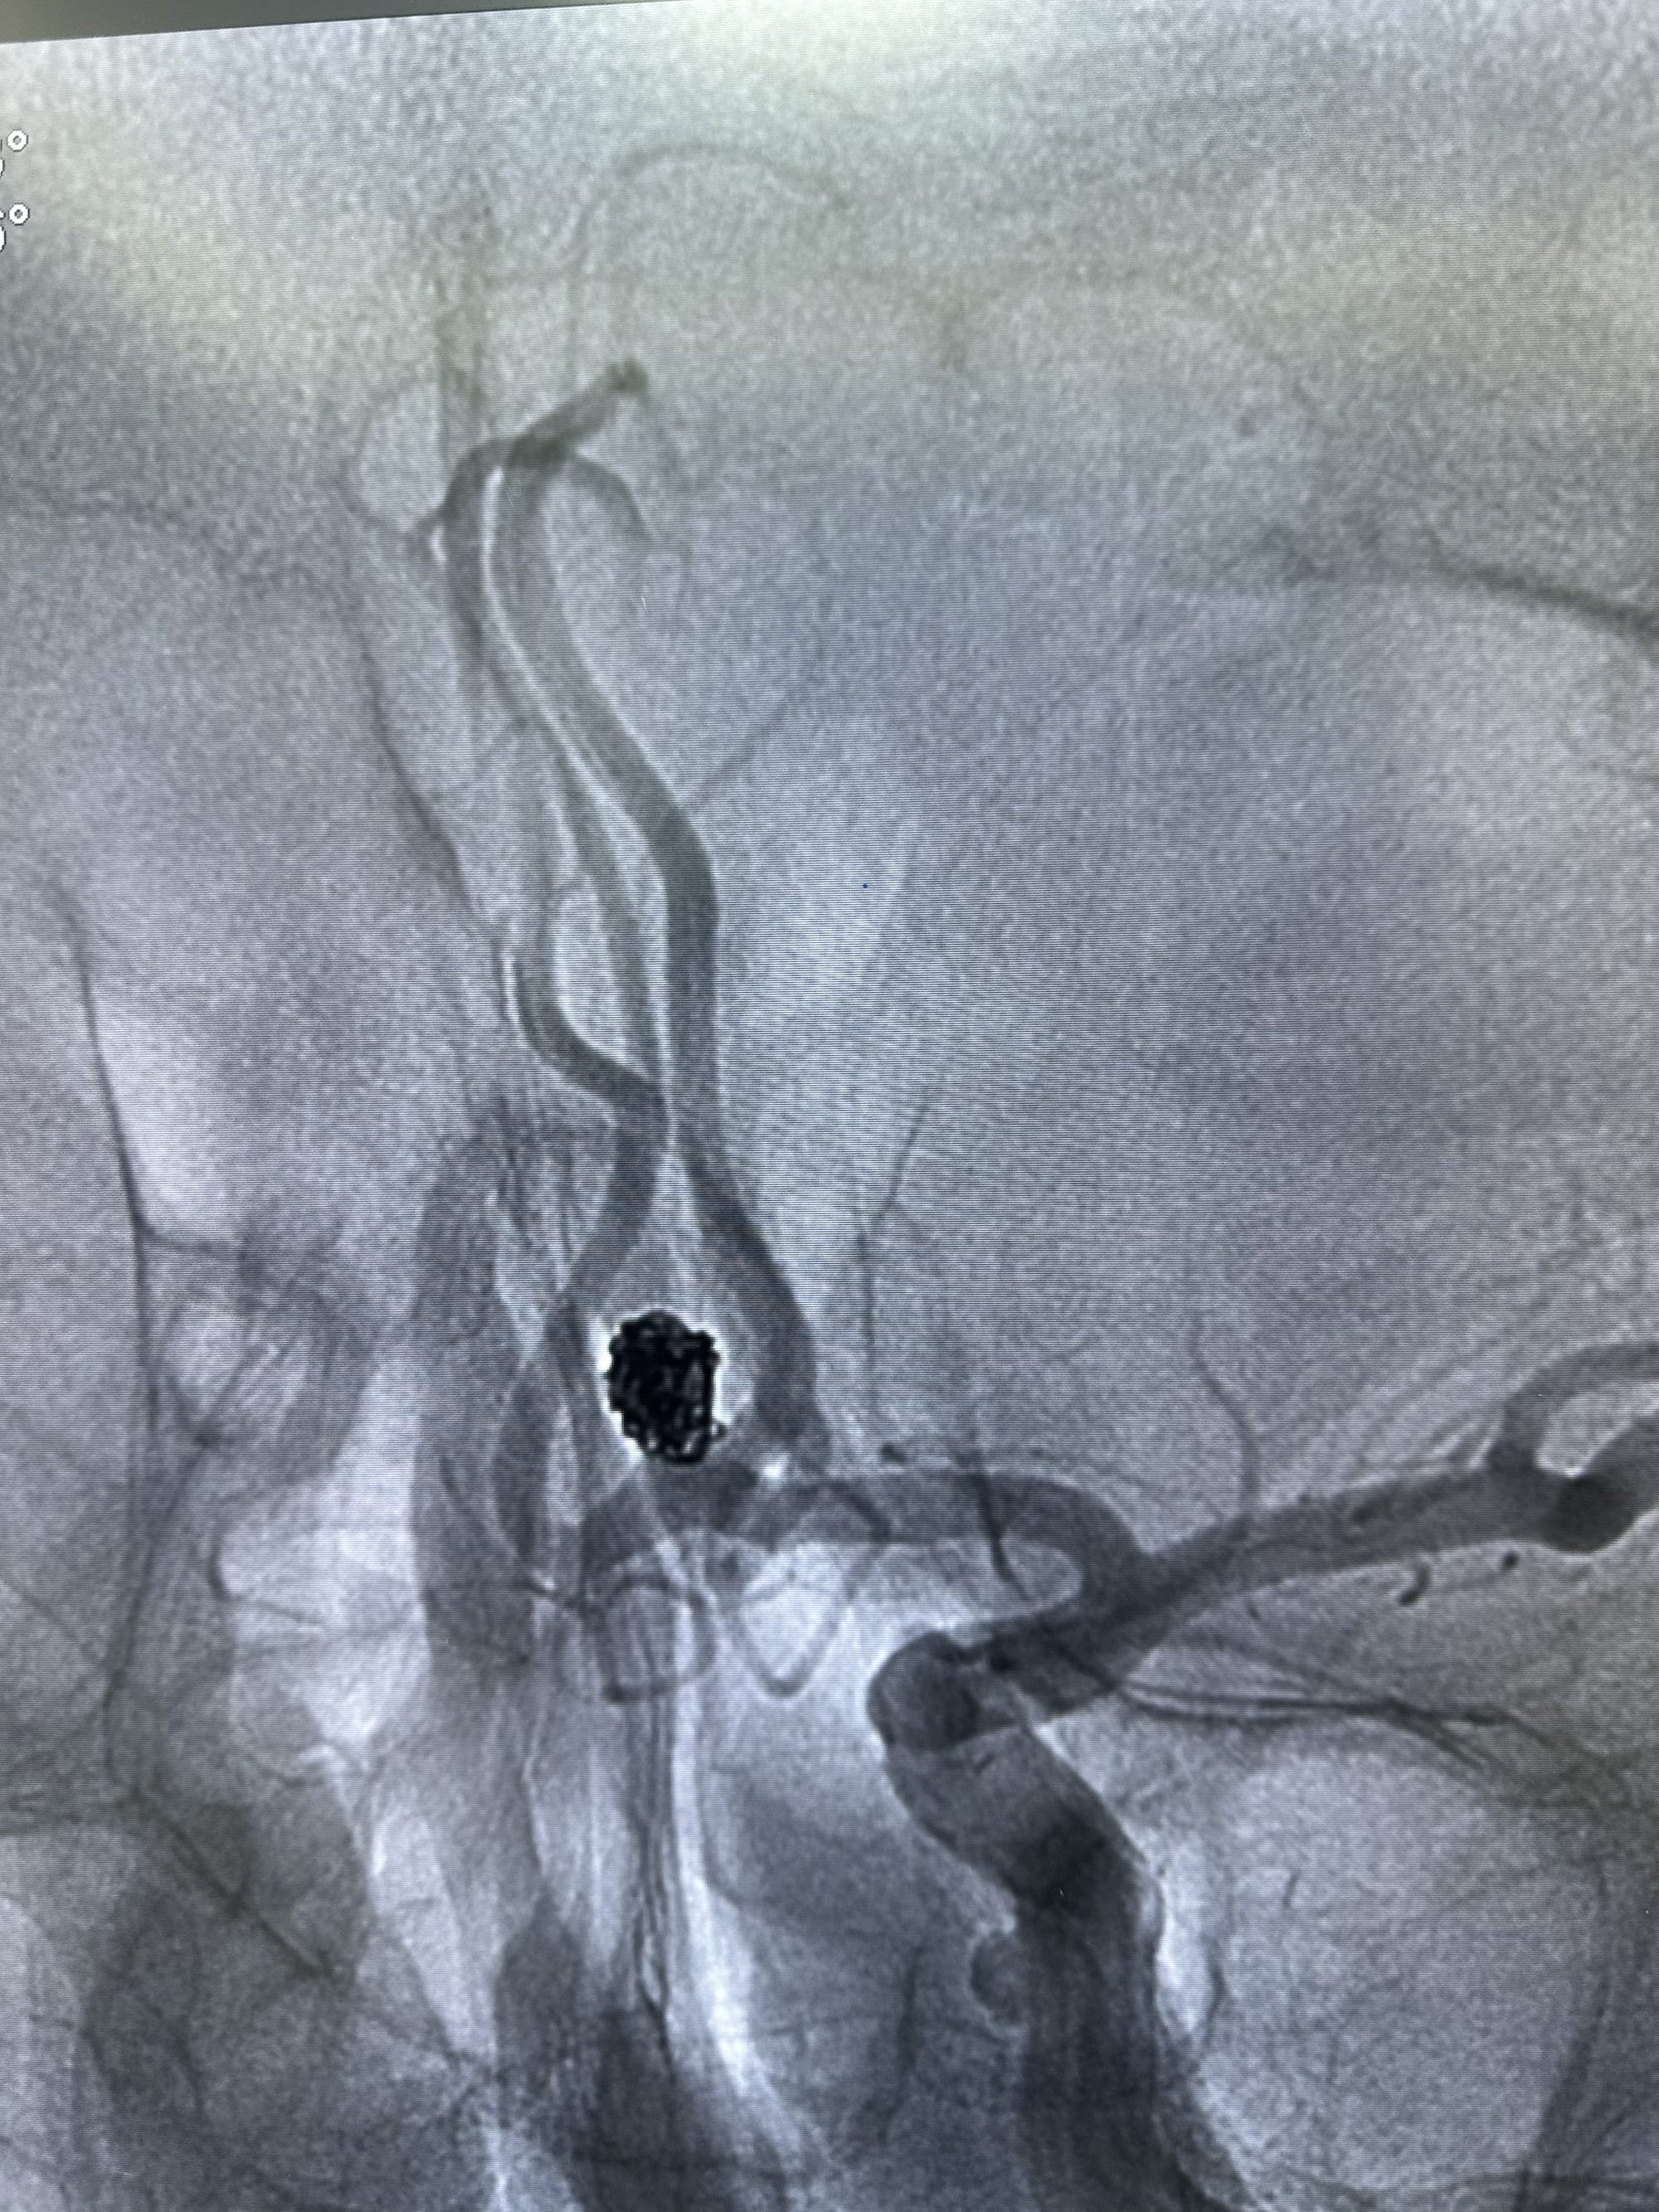

侧位